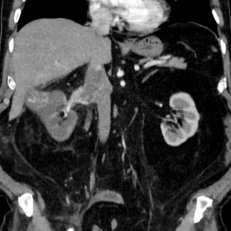

Онлайн-трансляция "Уникальная операция удаления тромба из нижней полой вены"

Россия, Москва

21-22 июн 2020

1263 просмотра